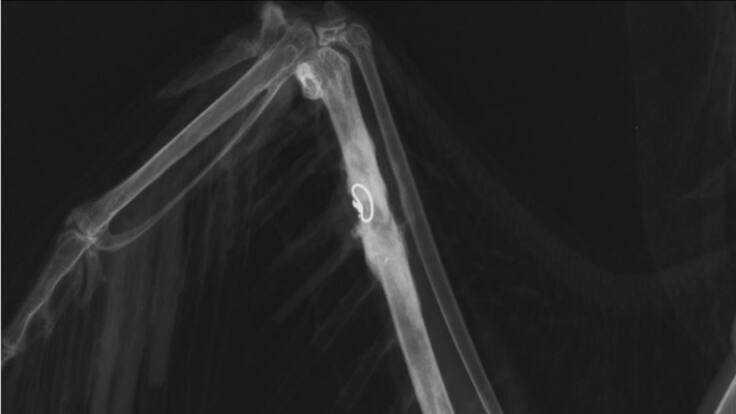

La asociación Acción por el Mundo Salvaje (AMUS) liberará este miércoles en el Parque Natural de Cornalvo un milano negro después de haberle practicado una operación por la que se le ha implantado un hueso de otro ave salvaje fallecido.

La operación quirúrgica a esta ave forma parte del proyecto del banco criogénico en rapaces, desarrollado en la recién creada plataforma Avian Medicine Research, que han puesto en marcha AMUS y la CREW Foundation y con la que están consiguiendo logros en pacientes aviares, según ha explicado en una nota la asociación extremeña.

La liberación de este ejemplar supone "la validación" de un injerto de hueso realizado en un milano negro liberado, lo que, según AMUS, "fundamenta y justifica este proyecto tan innovador en un escenario internacional que ya está revalorizando la medicina quirúrgica en aves salvajes".